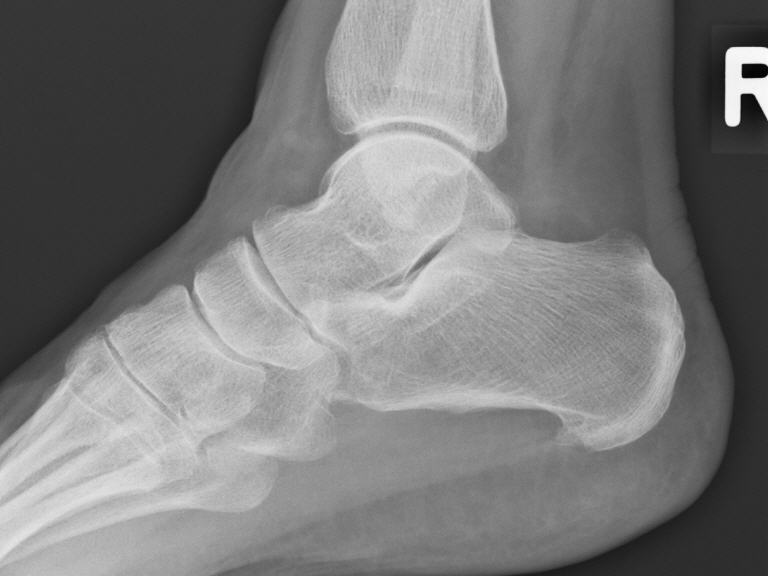

Die Röntgenreizbestrahlung ist eine spezielle Therapieform, bei der schwache Röntgenstrahlen gezielt eingesetzt werden, um schmerzhafte Entzündungen, wie z. B. bei Arthrose, Sehnenreizungen oder einen Fersensporn, zu behandeln. Die Strahlen wirken entzündungshemmend und schmerzlindernd, ohne das umliegende Gewebe stark zu belasten. Die Behandlung ist schmerzfrei, dauert nur wenige Minuten und erfolgt in mehreren Sitzungen. Die Strahlendosis ist dabei sehr gering, sodass die Therapie gut verträglich ist.

- Röntgenbestrahlung der Knochen, Bänder und Gelenke.